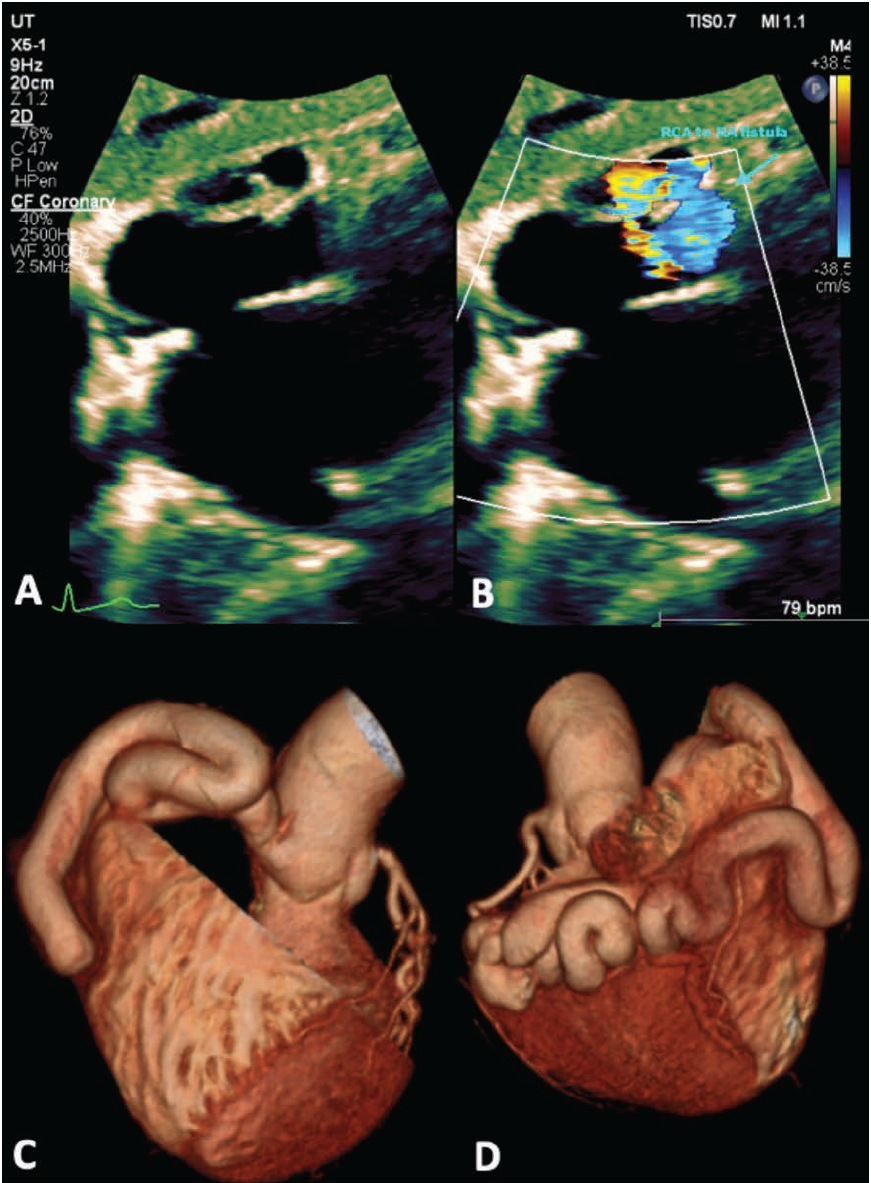

The echocardiogram results revealed an intact right coronary cusp and a normal ejection fraction, estimated to be 60%-65%. Mild tricuspid regurgitation was noted. Most notably, a right coronary aneurysm was appreciated, which communicated with the right atrium through a fistula (Figure 1A-D). A dilated coronary sinus was also noted.

Computed tomography angiography (CTA) of the coronary arteries revealed a stable/moderate tortious right coronary to right atrial fistula with a maximum transverse dimension of 15 mm distal to the ostia. A right heart catheter revealed a pulmonary to systemic flow ratio (Qp:Qs) of 1.4, signifying moderate shunting between the right coronary artery and the right atrium.